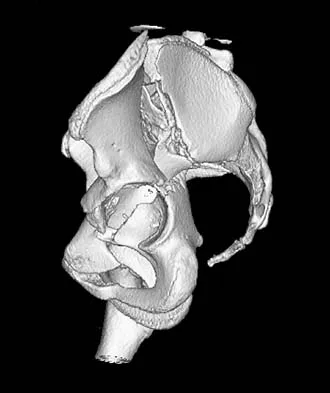

Figure 2 shows the radiograph of a 72-year-old woman who reports pain after a fall. History includes several years of increasing thigh pain and limb shortening. Management consisting of an extensive work-up for infection reveals normal laboratory studies, a positive bone scan, and a negative hip aspiration. What is the most likely etiology of this complication?

Explanation

The patient has a midstem periprosthetic fracture, which commonly results in loosening of the prosthesis. Patients who have a large amount of bone loss may require an allograft with the surgical reconstruction. Although the patient reported a fall, her history is also consistent with preexisting loosening of the prosthesis. Chronic infection has been shown in up to 16% of these fractures; however, the patient's work-up revealed no infection. Garbuz DS, Masri BA, Duncan CP: Periprosthetic fractures of the femur: Principles of prevention and management, in Cannon WD Jr (ed): Instructional Course Lectures 47. Rosemont, IL, American Academy of Orthopaedic Surgeons, 1998, pp 237-242. Bethea JS III, DeAndrade JR, Fleming LL, Lindenbaum SD, Welch RB: Proximal femoral fractures following total hip arthroplasty. Clin Orthop 1982;170:95-106.